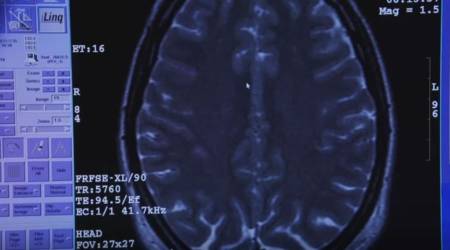

Por supuesto, antes de llevar a cabo la intervención es necesario que los candidatos se sometan a un estudio prequirúrgico para medir su rendimiento cognitivo y la actividad cerebral.

La doctora Nuria Esther Martínez Moreno, especialista en Radiocirugía Gamma, nos detalla que la máquina empleada en este tipo de cirugías concentra los haces radiados en la zona a tratar, y lo que se consigue es modular la función cerebral para anular la obsesión. O lo que es lo mismo, el paciente deja de sentir la sensación de ansiedad que antes le producía, en este caso, la comida.

Durante la operación tiene lugar un proceso llamado "Neuromodulación" mediante el cual permanece intacta la función de la célula pero se alteran sus cualidades de conectividad.